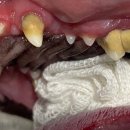

솔직한 후기입니다. 중랑구동물병원 강아지 침 흘림 문제를 해결하는 방법! ​ ​ 강아지가 갑자기 침을 많이 흘린다면 견주로서 걱정스러울 수밖에 없습니다. 강아지의 침 흘림은 여러 가지 원인에 의해 발생할 수 있으며, 때로는 건강에 이상이 있다는 신호일 수도 있습니다. 중랑구동물병원에서 강아지가 침을 흘리는...